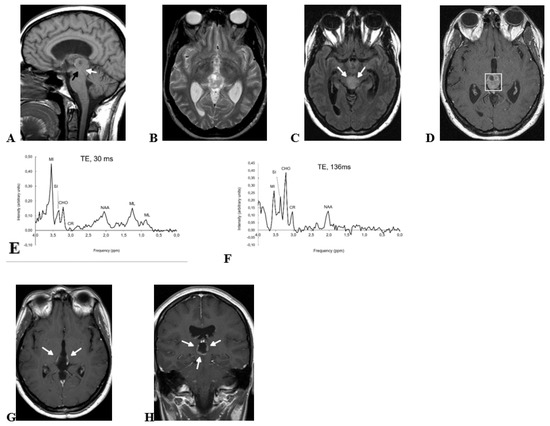

2.1. Case 1

2.2. Case 2